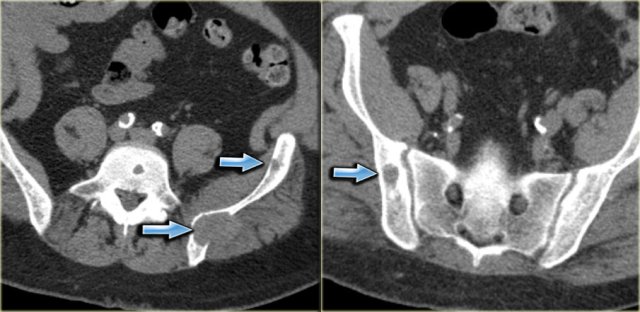

On the left a CT-image of a patient with multiple myeloma.

Notice the numerous osteolytic lesions and permeative cortical destruction pattern.

In the left sacral wing there is a larger lesion with a high density due to replacement of fatty bone marrow by myeloma (red arrow).